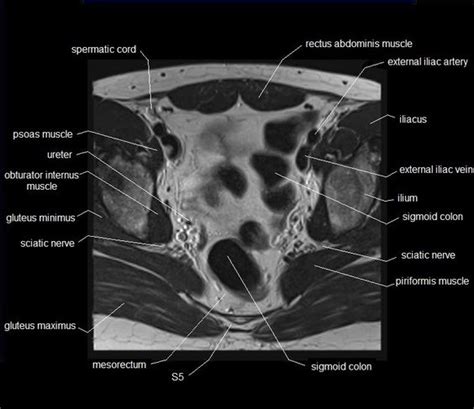

MRI pelvis anatomy | free male pelvis axial anatomy

MRI pelvis anatomy | free male pelvis axial anatomy from mrimaster.com

Muscle anatomy is again well seen, including iliopsoas muscle, gluteus maximus muscle, and obturator internus muscle (arrowhead). Best pract res clin obstet gynaecol. The muscles of the pelvis, hip and buttock anatomical chart. Muscles of the pelvis that cross the lumbosacral joint to attach onto the trunk were described in the previous blog post note: Anatomical drawing of the female pelvis. 3 enumerate the muscles of true pelvis. In front it is incomplete, presenting a wide interval between the anterior borders of the ilia. The ligament around this joint relaxes during pregnancy.

This section of the website will explain large and minute details of axial male pelvis use the mouse scroll wheel to move the images up and down alternatively use the tiny arrows (>>) on both side of the image to move the images. The lateral superficial muscles, the transversus and external and internal oblique muscles, originate on the rib cage and on the pelvis (iliac crest and inguinal ligament) and are attached to the anterior and posterior layers of the sheath of the rectus. Pelvis muscles mri anatomy / mri female pelvis anatomy axial image 16 | pelvis anatomy. Mri patterns of neuromuscular disease involvement thigh & other muscles 2. Normal anatomy, variants and checklist.